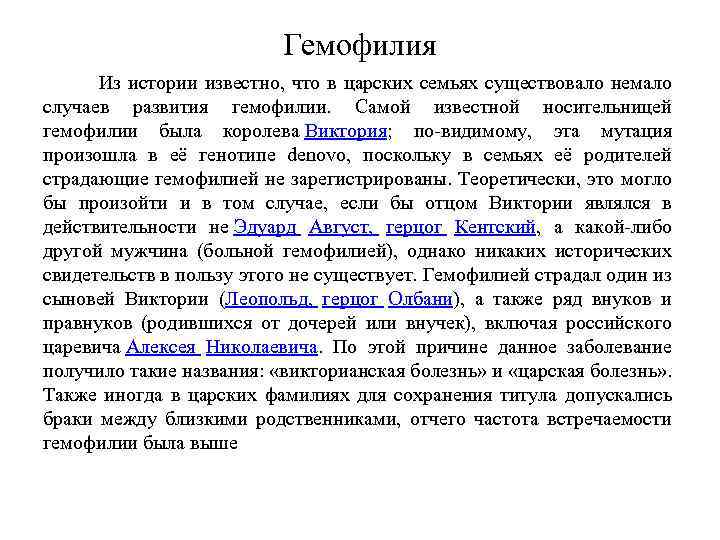

Геморрагические диатезы (2 уровень) В этом разделе мы изучаем три заболевания: 1. Аутоиммунная тромбоцитопеническая пурпура 2. Гемофилия 3. Геморрагический васкулит. В обеспечении нормального гемостаза участвуют тромбоциты (тромбоцитарный компонент), факторы свертывания крови (плазменный компонент) и сосудистая стенка (сосудистый компонент). Фибринолитическая система обеспечивает растворение избыточных тромботических масс

лекцйииГематология(15-16).ppt